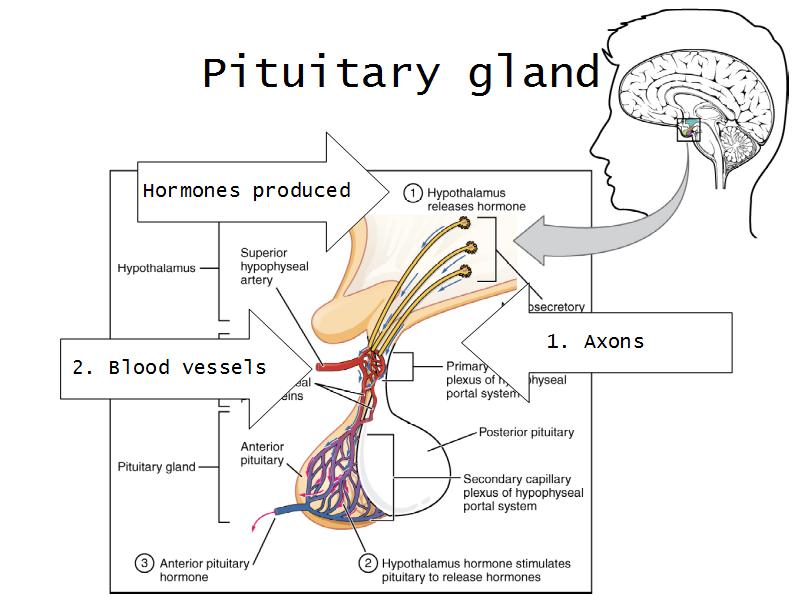

Pituitary gland

How does the pituitary and hypothalamus communicate?2 ways